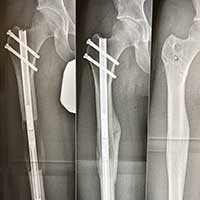

Since 2011, we have been using internal bone lengthening. This has been the most significant advance in our field in the last decade. With the use of an internal lengthening nail, we can avoid the use of external fixation entirely. With bone lengthening, we perform an osteotomy (bone cut) and gradually pull the bone apart very slowly with a regular rate and rhythm. Since bone has the ability to regenerate, new bone gradually grows in the space leading to bone elongation. In the past, we could use only external fixation to gradually lengthen the bone, but now the internal lengthening nail has replaced external fixation for most long bone lengthening surgeries. A telescopic rod in inserted into the marrow cavity of the bone. A remote control device spins a magnet in the rod which turns a gear and elongates the rod which lengthens the bone. The internal method is very accurate and is safer and more comfortable for the patient compared to external fixation.

Tibia Lengthening with PRECICE Internal Lengthening Nail

Femur Lengthening with Precice Internal Lengthening Nail